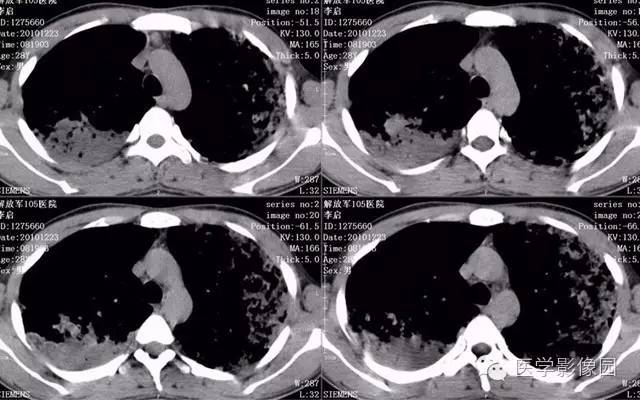

弥漫性肺泡细胞癌1例CT影像表现

病理结果:弥漫性肺泡细胞癌

弥漫性肺泡癌的主要临床及CT表现:临床表现无明显特征, 随着病情的进展, 咳嗽、 咳白痰、 进行性气促。CT表现 为病变分布有两种情况:病变累及一个肺段或肺叶;病变广泛分布于两肺。可归纳为5个特征性征象:蜂房征;支气管充气征;磨玻璃征;血管造影征;两肺弥漫分布的斑片状与结节影。